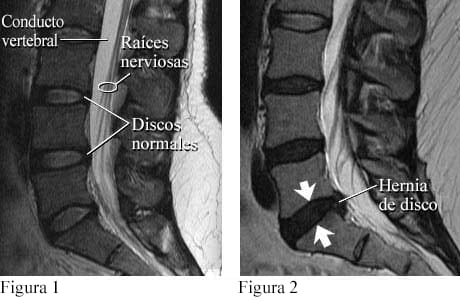

La imagen es cortesía de Intermountain Medical Imaging, Boise, Idaho. Todos los derechos reservados.

Una vista lateral de la columna lumbar muestra discos, conducto vertebral y raíces nerviosas normales (ver figura 1). Las raíces nerviosas normalmente flotan en el conducto lleno de líquido. La figura 2 muestra una pequeña hernia de disco que sobresale en el conducto en dirección a las raíces nerviosas.